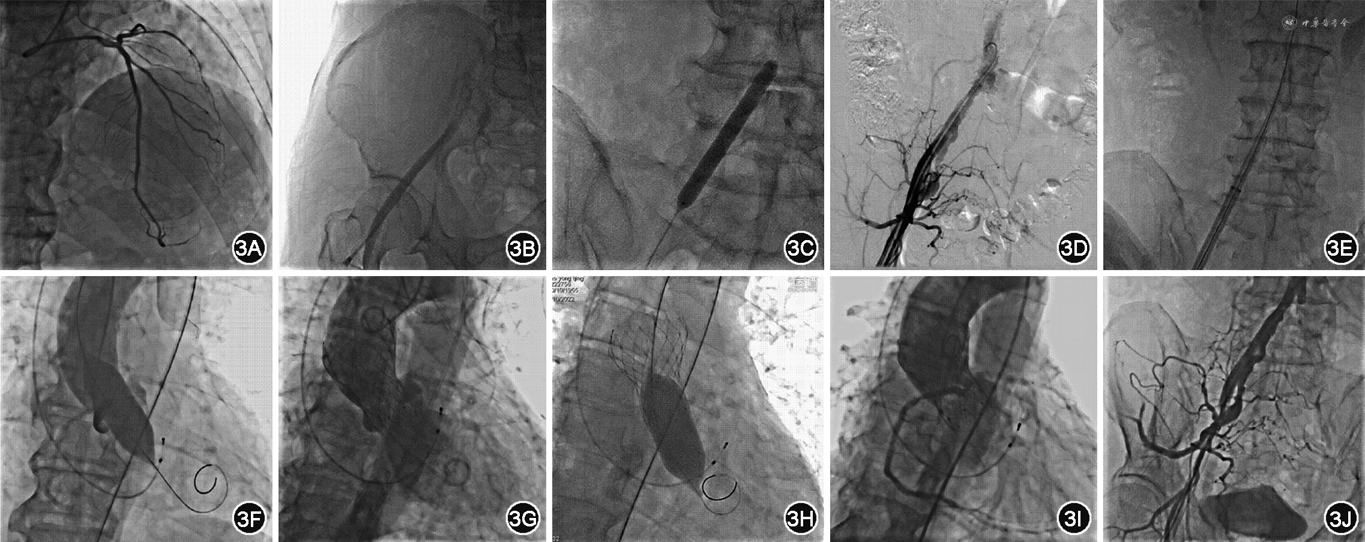

2022年10月10日患者局麻+适当镇静下行经皮冠状动脉造影术+经皮选择性右髂总动脉球囊扩张术(Shockwave冲击波球囊)+升主动脉造影术+临时起搏器植入术+经皮主动脉瓣扩张术+TAVR。患者取平卧位,穿刺左桡动脉测量动脉压,穿刺右颈内静脉作为补液入路,取右股动脉、右桡动脉及左锁骨下静脉为穿刺血管,常规消毒铺布,以1%利多卡因15 ml分别局部麻醉各穿刺点,以改良Seldinger′s术穿刺左锁骨下静脉,置入6 F动脉鞘,经左锁骨下静脉将临时起搏器电极送至右心室心尖部,测试起搏器起搏良好。以相同的方法穿刺右桡动脉,置入6 F动脉鞘。以5 F TIG-4.0左右共用造影导管及5 F JL造影导管分别行左、右冠状动脉造影,结果显示冠状动脉右优势型,左冠状动脉主干末端有30%局限性狭窄,左前降支中段有20%狭窄,第一对角支开口局限70%狭窄,心肌梗死溶栓试验(TIMI)血流3级(图3A);回旋支无明显狭窄,TIMI血流3级;右冠状动脉近段局限60%狭窄,TIMI血流3级。在透视下以改良Seldinger′s术成功穿刺右侧股总动脉,置入6 F股动脉鞘,预埋2把proglide缝合器,并更换8 F股动脉鞘,X线下由右侧股动脉鞘管送入6 F猪尾造影导管至腹主动脉右髂总动脉开口处行腹主动脉造影,提示右髂总动脉近段有弥漫性55%狭窄,合并近270°严重钙化(图3B)。随后利用Shockwave冲击波球囊行经皮选择性右髂总动脉球囊扩张术。首先,经8 F股动脉鞘,送SION blue导丝通过右髂总动脉近段的局限性狭窄病变达腹主动脉,然后用7.0 mm×60 mm Shockwave冲击波球囊(健适医疗,中国上海)先后以4、6 atm(1 atm=101.325 kPa)的压力分别对右髂总动脉近段进行微波震荡约20 s(图3C)。复查造影提示右髂总动脉残余狭窄30%,钙化影减轻,无造影剂滞留或外漏,未见夹层影像学改变(图3D)。X线下由右侧桡动脉鞘管送入6 F猪尾造影导管至主动脉根部行升主动脉造影,了解主动脉瓣、冠状动脉和主动脉弓形态,然后经右侧股动脉鞘管经Lungderquist特硬导丝引导更换为GORETM 20 F导引鞘(图3E),经右侧股动脉送入AL2造影导管至升主动脉,在直头导丝引导下跨瓣成功,交换J型导丝,再送入6 F猪尾导管至左心室,测量左心室压力为240/3 mmHg,升主动脉压力150/66 mmHg,跨瓣压差为90 mmHg,交换Lungderquist特硬导丝至左心室,撤出猪尾导管。临时起搏器以5 V、150~180次/min频率起搏控制性降压,用直径为23 mm球囊预扩张主动脉瓣,扩张同时行主动脉根部造影,结果显示主动脉瓣处无明显反流,冠状动脉血流未受影响(图3F)。退出球囊,送入29 A的Venus Plus主动脉瓣支架(启明医疗,中国杭州),成功跨瓣后精确定位,缓慢释放瓣膜支架前1/3,并在临时起搏器以180次/min频率起搏控制血压下逐步精确释放主动脉瓣膜支架。复查升主动脉造影,见人工主动脉瓣贴壁不良,未见内漏,但有中度瓣周漏(图3G)。因瓣膜释放后有中度瓣周漏,透视下可见瓣膜褶皱,遂用25号球囊后扩张(图3H)。复查升主动脉造影,见人工主动脉瓣贴壁良好,未见内漏及瓣周漏,左右冠状动脉开口均未受影响,显影良好(图3I)。再次测量左心室压力为146/18 mmHg,升主动脉压力143/63 mmHg,跨瓣压差为3 mmHg,同时行经胸超声心动图检查证实置入的主动脉瓣工作良好,无明显反流现象。最后撤出股动脉鞘,复查造影入路未见损伤(图3J)。